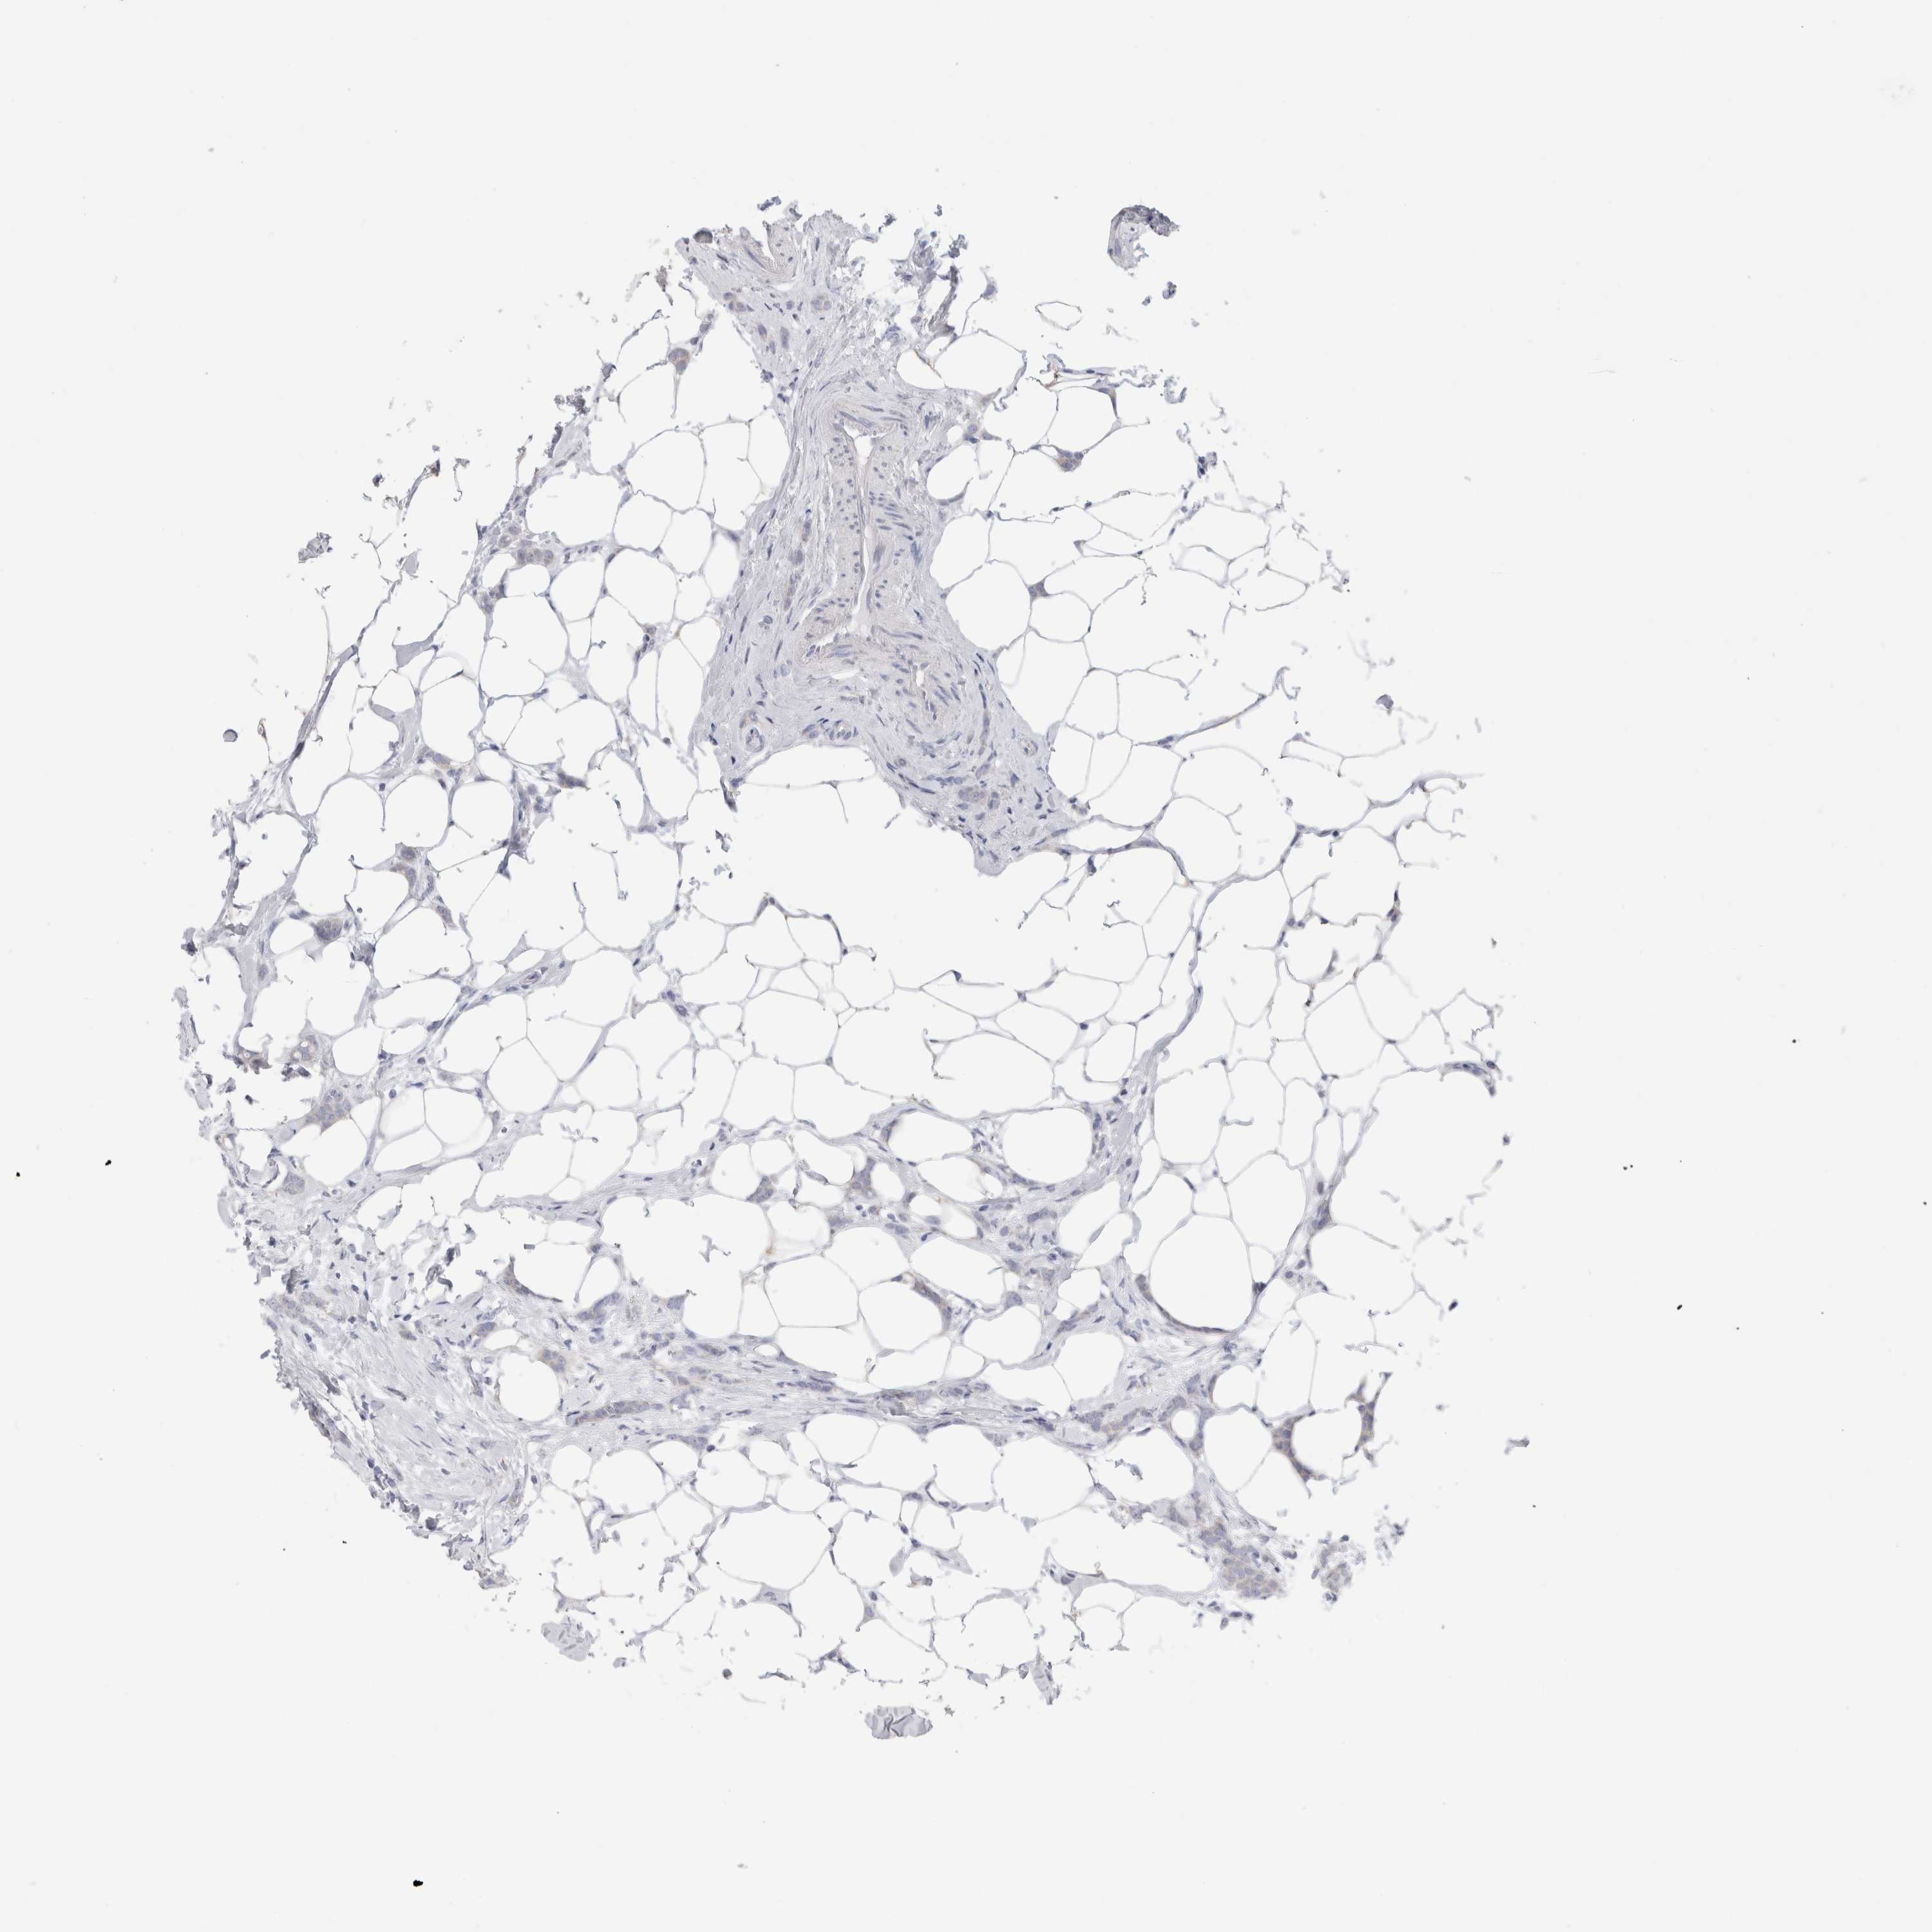

CANCER BREAST CANCER Show tissue menu

BRCA TCGA BRCA VALIDATION PROTEIN EXPRESSION